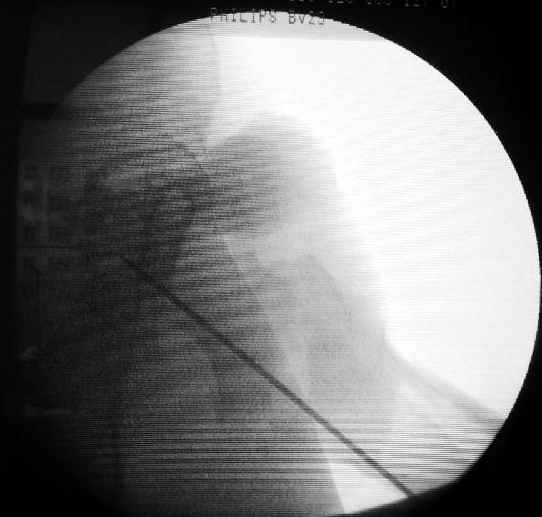

Второй случай тоже репозиция из малого доступа, больному 19 лет, множественные огнестрельные повреждениия конечностей, живота и черепа, правая конечность холодная, без пульсации. Ортопедический диагноз: огнестрельный перелом правого бедра. При срочной ангиографии повреждения сосудов не подтвердилось, конечность из-за ургентности состояния больного зафиксирована временным наружным фиксатором и больной оставлен на операционном столе для срочной лапаротомии хирургической службой.

Больной долго оставался нестабильным, только на 14 день удалось заменить на антеградный интромедуллярный штифт TFN (trochanteric femoral nail) SmithNephew. После неудачной попытки закрытой репозиции, несмотря на использование "joystick", проксимальный стержень от

наружного фиксатора, (перелом начал срастаться) репозицию провели из малого доступа, затем остальные этапы операции.

Случай был представлен из-за того, что больного оперировали после наружной фиксации и был риск инфекцирования через места проведения стержней (на снимках), прошло больше 3 месяцев, выписан из амбулаторной службы из-за отсутсвия надобности дальнейшего наблюдения.